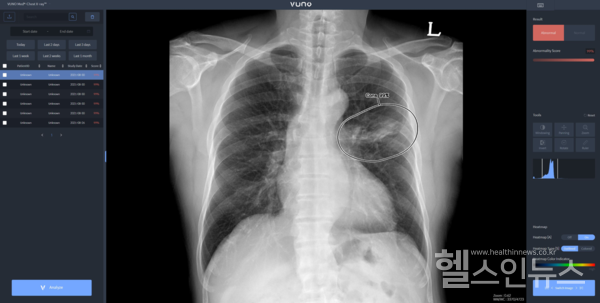

자이드 군 병원에 도입된 솔루션은 이동형 엑스레이 장비에 뷰노의 AI 기반 흉부 엑스레이 판독 보조 솔루션 뷰노메드 체스트 엑스레이™(VUNO Med®-Chest X-ray™)를 탑재한 패키지 제품이다. 별도의 차폐 시설 없이 다양한 상황에서도 쉽게 환자의 흉부 엑스레이 촬영을 할 수 있는 이동형 장비에 인공지능을 연동해 수 초 이내에 판독 결과를 확인할 수 있다는 회사측의 설명이다.